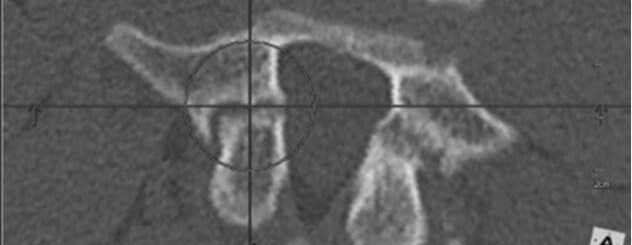

Koniecznie trzeba przeprowadzić dodatkową diagnozę. Idealna w tej sytuacji będzie tomografia, która znakomicie pokazuje kość i jej strukturę. Kręgoszczelina to taka malutka szczelinka, która ma mniej niż milimetr w obrębie kości. Problemem jest fakt, że dzieciom 13-, 14- czy 15-letnim badania tomografem nie wykonuje się, poza szczególnymi przypadkami, jak nowotwór. Pracownie rezonansu magnetycznego, m.in. w klinice Rehasport, mają specjalny program do obróbki obrazów rezonansowych. Nazywa się to rezonansem izowolumetrycznym i na jego podstawie obserwuje się kręgoszczelinę, bo daje obraz przestrzenny.